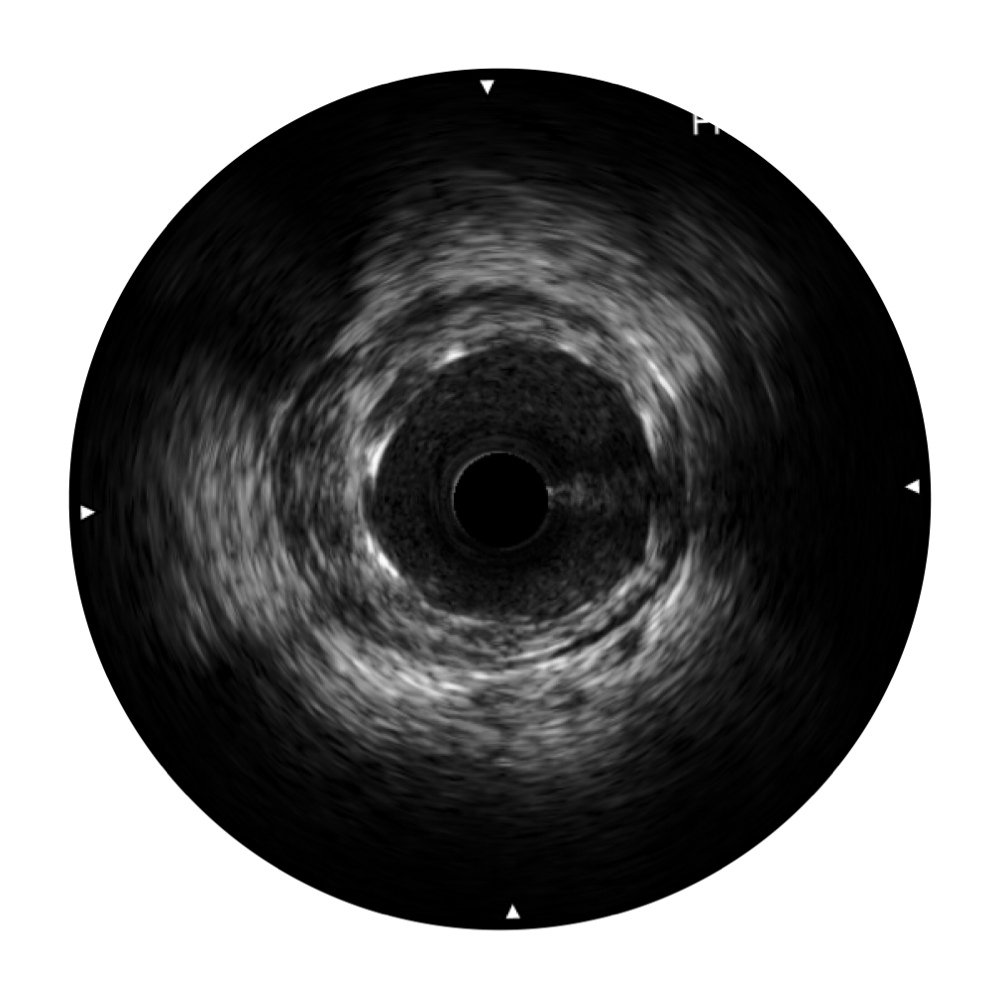

• 乐玩lewin国际宽频IVUS图像

• 传统IVUS图像

对比传统IVUS导管成像,乐玩lewin国际宽频IVUS图像的近场支架梁显影更细腻,远场中膜外血管仍清晰可辨,兼顾远中近,兼顾分辨力与穿透深度